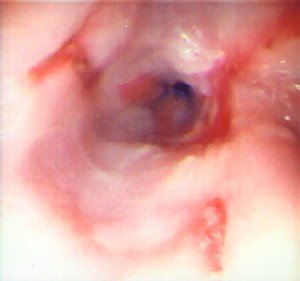

Pulsiyon divertikuldur. QB-nun boyun hissəsinin arxa divarında, selikli qişa və selikaltı əsasın əzələlər arasından kənara qabarması nəitcəsində əmələ gəlir. Üst ezofagus və ya farinqoezofageal divertikul da adlandırılır.

Diaqnostikası

Dəqiqləşdirmə

Diaqnozun dəiqiləşdirilməsi üçün kontrastlı Rentgenoloji müayinələr, KT və çox ehtiyatla endoskopiya edilir.

- Endoskopiya - divertikulun perforasiyası təhlükəsinə görə çox ehtiyatla aparılmalıdır.